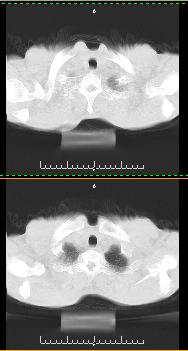

以下是引用liaoqiang在2008-3-21 17:45:00的发言:[br]右上叶尖段、后段有多发小结节和小条状影。考虑感染(结核可能性大。)。建议治疗后复查。

以下是引用王2008在2008-3-21 17:38:00的发言:[br]右上叶后段沿纹理走向呈串珠状.边缘欠清密度增高影,局部胸膜增厚.[br]考虑1.右上支扩可能.2.右上炎症.建议治疗后复查.请各位老师指教.

以下是引用lj11119999在2008-3-21 18:15:00的发言:[br]右上叶尖段、后段有多发小结节和小条状影。考虑感染(结核可能)建议进一步检查!